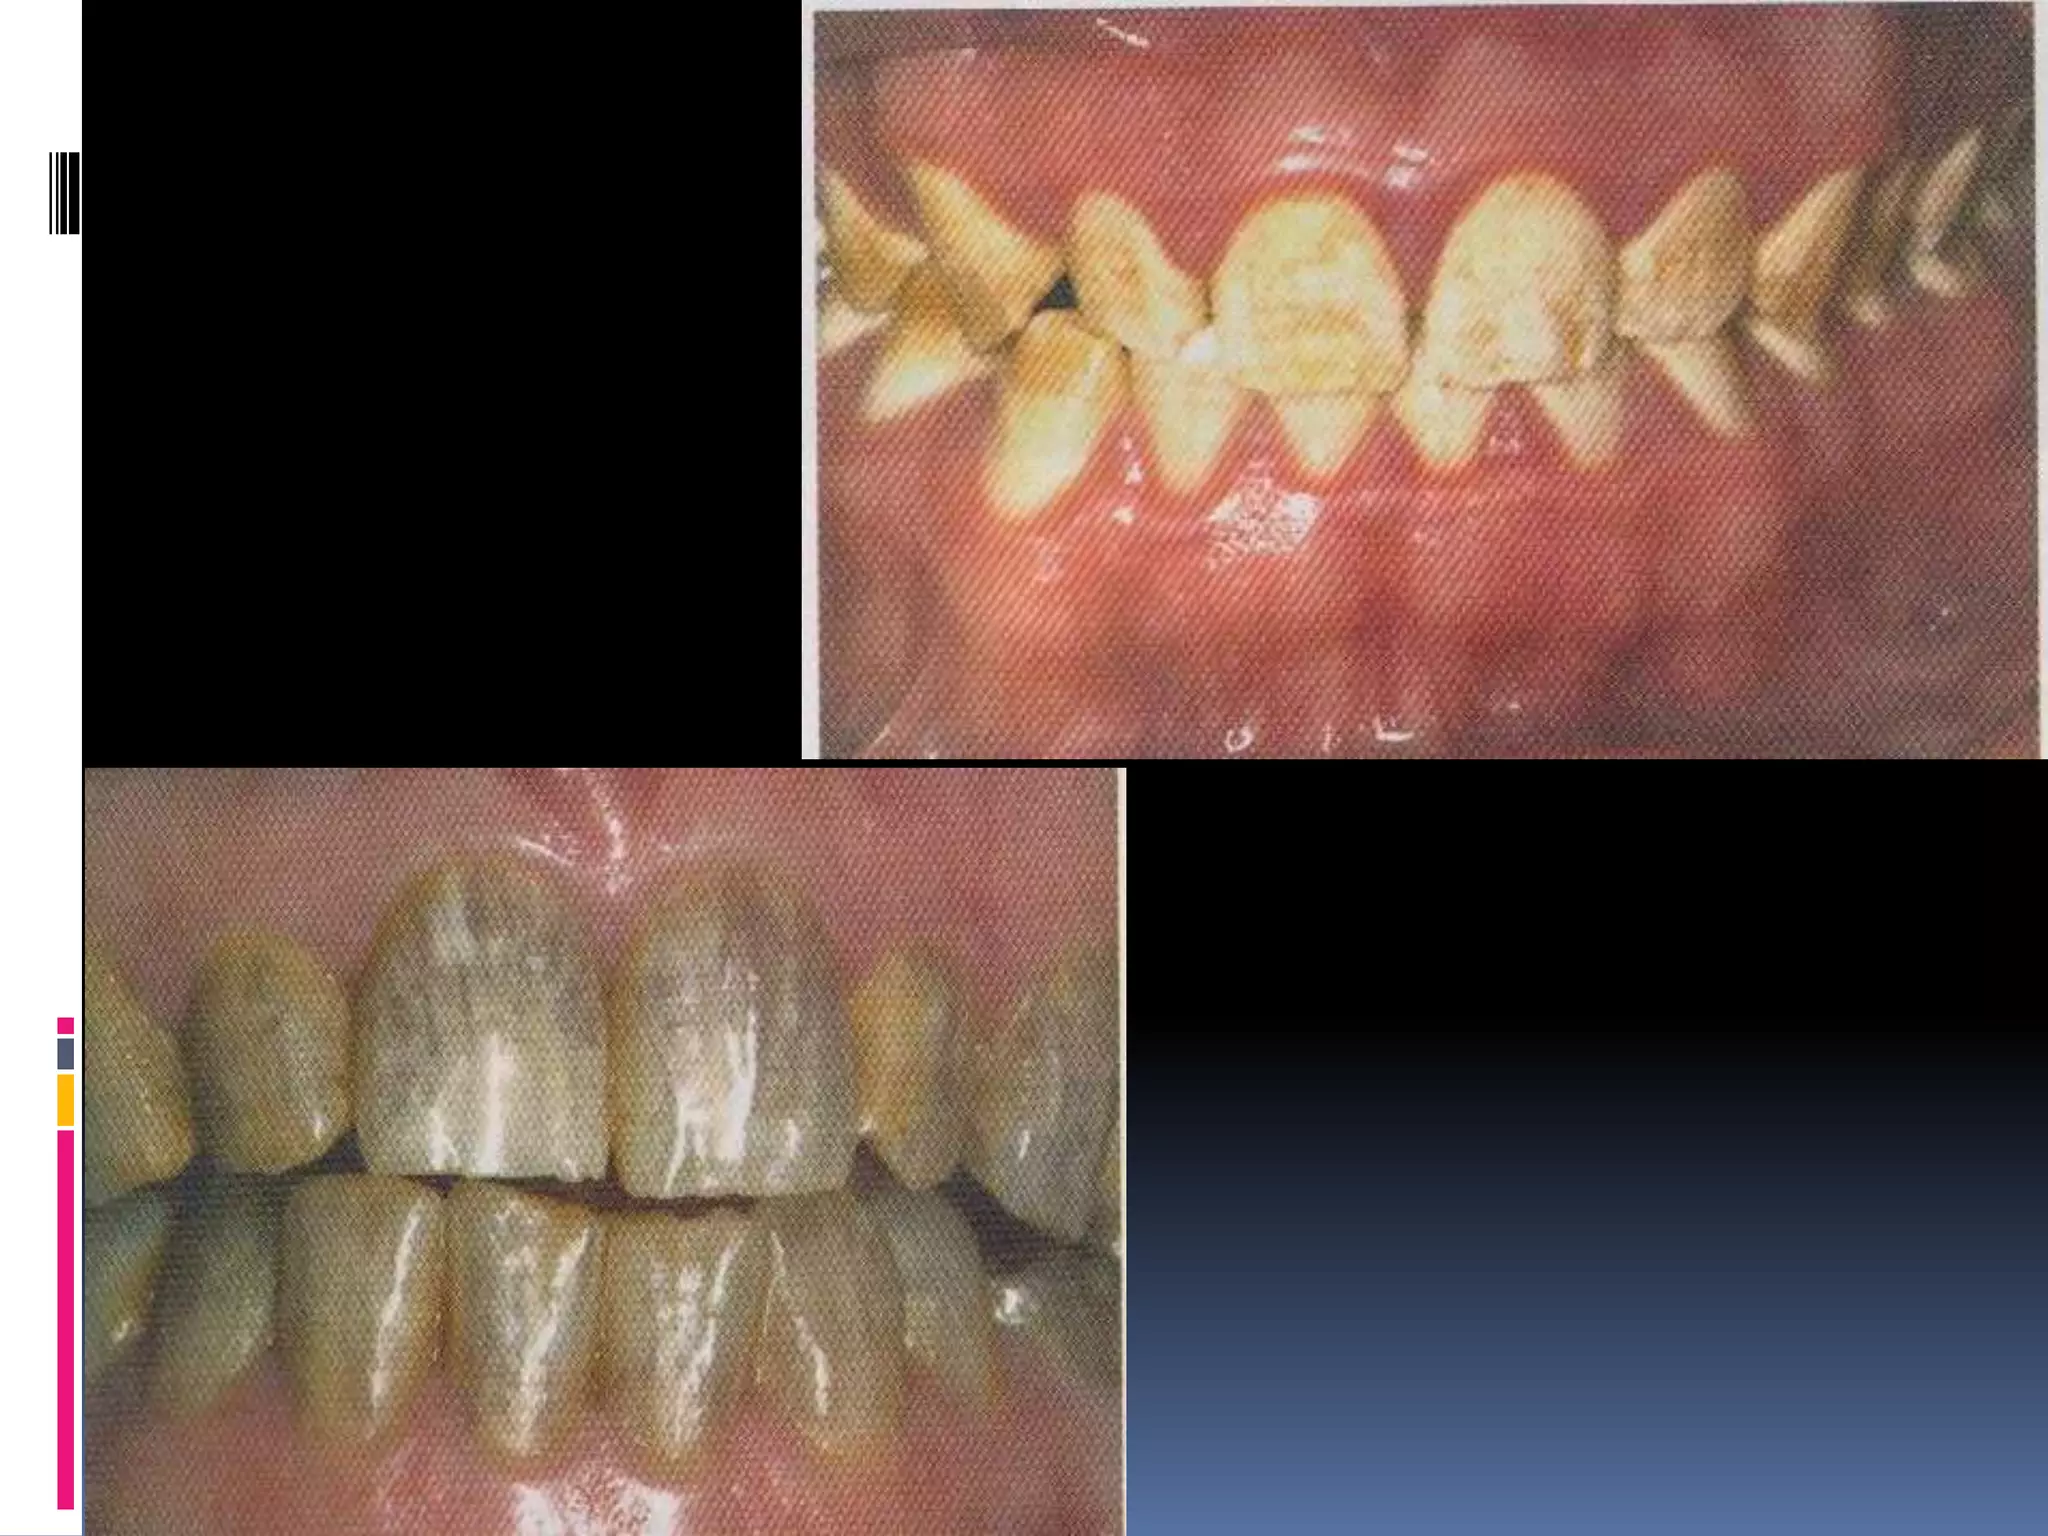

Hypocalcified

 Enamel matrix is laid down appropriately but

no mineralization.

 Enamel is soft & easily lost.

 Yellow – brown / orange but exhibit stained

brown- black.

 Coronal enamel is removed with cervical

portion calcified